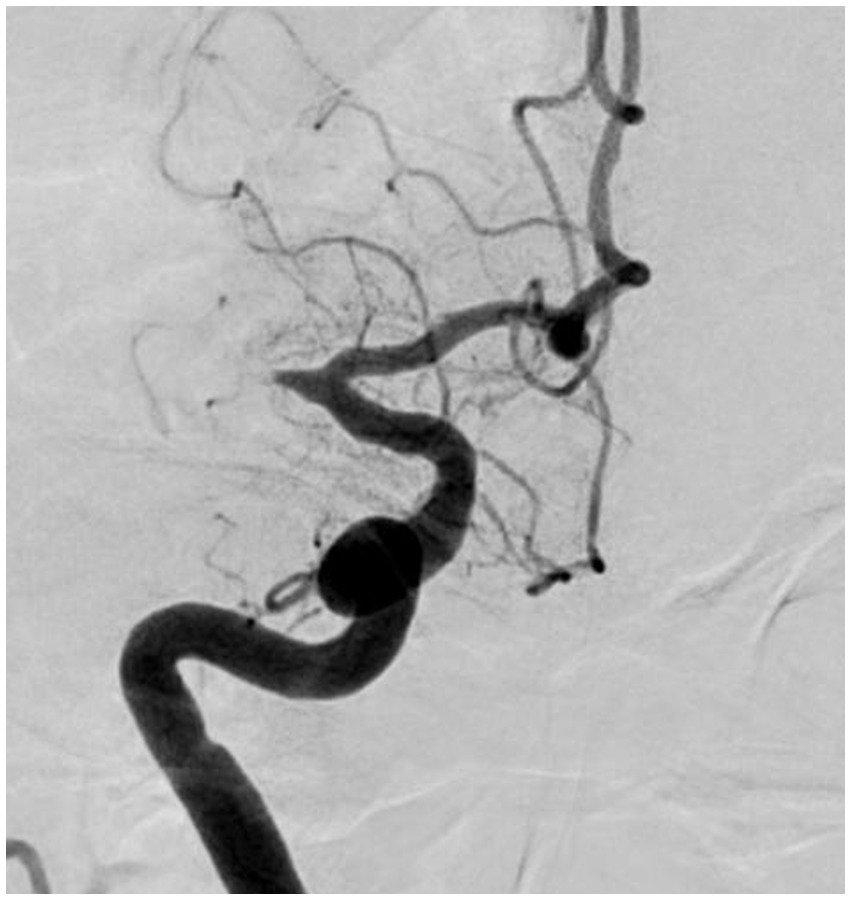

4.1. Significant fixed focal stenosis after reperfusion

“Fixed focal stenosis of substantial magnitude” has been proffered as a diagnostic hallmark of ICAS-related LVO (Figure 4) (34). This criterion is articulated as “a concentration of significant stenosis circumscribed to the site of occlusion,” as observed on postoperative or definitive imaging of the MCA and was initially a term employed to characterize ICAS-related LVO. Although few systematic investigations have focused on fixed focal stenosis, a Korean registry utilizing stent retrievers noted an incidence of approximately 15–20% (35).

Figure 4

Significant fixed focal stenosis. A 59-year-old man was diagnosed with significant fixed focal stenosis. The right MCA M1 occlusion was recanalized in a single pass with a stent retriever, but the site of occlusion was found to have a fixed focal stenosis. MCA, middle cerebral artery.